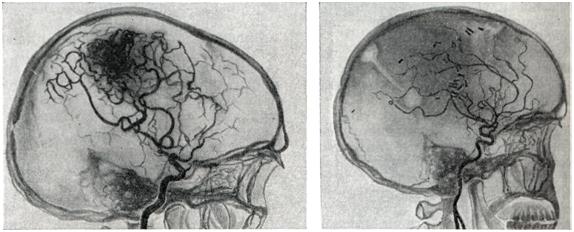

Диагноз.Появление перечисленных выше симптомов в молодом возрасте (чаще на 2—3-м десятилетии жизни) дает основание для предположения артерио-венозной аневризмы. Диагноз может быть поставлен лишь на основании всестороннего ангиографического исследования. Для выявления приводящих артерий и рано заполняющихся дренирующих вен необходима серийная ангиография с наибольшим числом снимков в первые 2—3 секунд. Лечение.Консервативное лечение является по существу симптоматическим и заключается в применении противосудорожных препаратов: фенобарбитал, дилантин и другие. При кровоизлияниях необходимо проведение коагулянтной и гипотензивной терапии. Лучевая терапия при артерио-венозных аневризмах неэффективна. Радикальным методом лечения является полное иссечение артерио-венозной аневризмы (рис. 4). Однако при большой распространенности аневризм и их расположении в глубинных, жизненно важных структурах мозга такая операция может оказаться невыполнимой. В подобных случаях могут применяться операции, уменьшающие приток крови к аневризме или приводящие к частичному выключению аневризмы,— окклюзия приводящих артерий, эмболизация артерио-венозной аневризмы и некоторые другие. Показания к той или иной операции должны быть строго индивидуальными; они определяются особенностями клинического течения, в частности количеством и тяжестью перенесенных кровоизлияний, локализацией, распространенностью аневризмы, характером ее кровоснабжения и опытом хирурга. В связи с совершенствованием техники операций, в частности широким использованием микроваскулярпой техники, показания к радикальному удалению артерио-венозных аневризм ставятся более широко, в том числе и при аневризмах, располагающихся в функционально важных зонах (речевой, двигательной). При радикальном удалении крупных, богато васкуляризируемых аневризм операцию следует начинать с выключения приводящих артерий. Благодаря этому уменьшается кровенаполнение аневризмы, а следовательно, меньше кровопотеря. При небольших поверхностно расположенных артерио-венозных аневризмах допустимо первоначальное выключение дренирующей вены; аневризма при этом наполняется кровью и более четко контурируется. Удаление аневризм, особенно расположенных в функционально важных областях, следует производить, выделяя сосудистый клубок по границе с мозгом, оставляя на поверхности аневризмы лишь тонкий слой измененного мозгового вещества. Важно при этом все время манипулировать вне пределов сосудистого клубка аневризмы, поскольку повреждение целостности ее сосудов приводит к сильному кровотечению, которое трудно остановить. Наличие внутримозговых гематом облегчает обнаружение аневризмы. Иногда гематомы как бы отслаивают часть аневризмы от мозга и тем самым упрощают ее удаление. При небольших глубоко расположенных аневризмах для облегчения их обнаружения во время операции могут быть использованы принципы стереотаксической нейрохирургии. Предварительно на основании расчетов по ангиограммам в область расположения аневризмы вводится направитель, по которому затем осуществляется подход к ней. При невозможности радикального удаления аневризмы может быть применено выключение приводящих артерий. Хотя этим путем обычно не удается достигнуть излечения и спустя некоторое время развиваются новые источники кровоснабжения артерио-венозной аневризмы, такая операция может привести к ослаблению кровотока в ней и уменьшить возможность повторных кровоизлияний. При больших, богато васкуляризированных аневризмах может быть осуществлена эмболизация сосудов аневризмы с помощью рентгеноконтрастных эмболов. С этой целью обычно используются различного размера пластиковые шарики, которые вводят через обнаженную на шее сонную (иногда вертебральную) артерию. В связи с резким ускорением тока крови в аневризме эмболы устремляются в ее сосуды. Таким образом иногда удается выключить из кровообращения значительную часть артерио-венозной аневризмы (рис. 5). Выполнение подобной операции требует точных представлений о характере кровоснабжения аневризмы, о диаметре, месте отхождения приводящих артерий и прочего. Каждый этап операции нужно контролировать повторным ангиографическим исследованием. Несоблюдение этих предосторожностей может привести к попаданию эмболов в нормальные сосуды мозга. Для направленного выключения сосудов, кровоснабжающих аневризму, а также для лечения других сосудистых поражений мозга (каротидпокавернозные соустья, некрые формы артериальных аневризм) применяют так называемые ангиотаксические операции. Смысл этих операций заключается в том, что подход к пораженному участку осуществляется по кровеносному руслу внутри просвета сосуда. С этой целью используют специальные катетеры, снабженные окклюзирующим баллончиком (Ф. А. Сербиненко, 1971). Такой катетер может быть направленно введен в приводящий сосуд артерио-венозной аневризмы посредством пункции сонной артерии на шее. Конструкция катетера позволяет произвести окклюзию сосуда, оставив в артерии баллончик, заполненный быстротвердеющим пластическим веществом, а катетер извлечь (рис. 6). Делаются попытки хирургического лечения артерио-венозных аневризм путем их замораживания с помощью жидкого азота. При аневризмах большой вены мозга, вызывающих окклюзию путей цереброспинальной жидкости, если нет условий для их удаления, возникают показания для разгрузочной операции с отведением цереброспинальной жидкости из желудочков мозга в венозное русло (вентрикуло-аурикулостомия). При тотальном удалении артерио-венозной аневризмы полностью исчезает опасность повторных кровоизлияний, прекращаются или становятся реже эпилептические припадки. Наступает нормализация кровообращения в головном мозге: при контрольном ангиографическом исследовании отмечается нормализация просвета ранее расширенных артерий, не заполняются дренирующие вены, лучше контрастируются сосуды областей мозга, прилегавших к аневризме. Летальность при тотальном удалении артерио-венозных аневризм колеблется в широких пределах и определяется прежде всего показаниями для хирургического лечения. По литературным данным, средняя послеоперационная летальность составляет приблизительно 10%, но при правильном определении показаний и использовании современных хирургических возможностей могут быть достигнуты лучшие результаты.